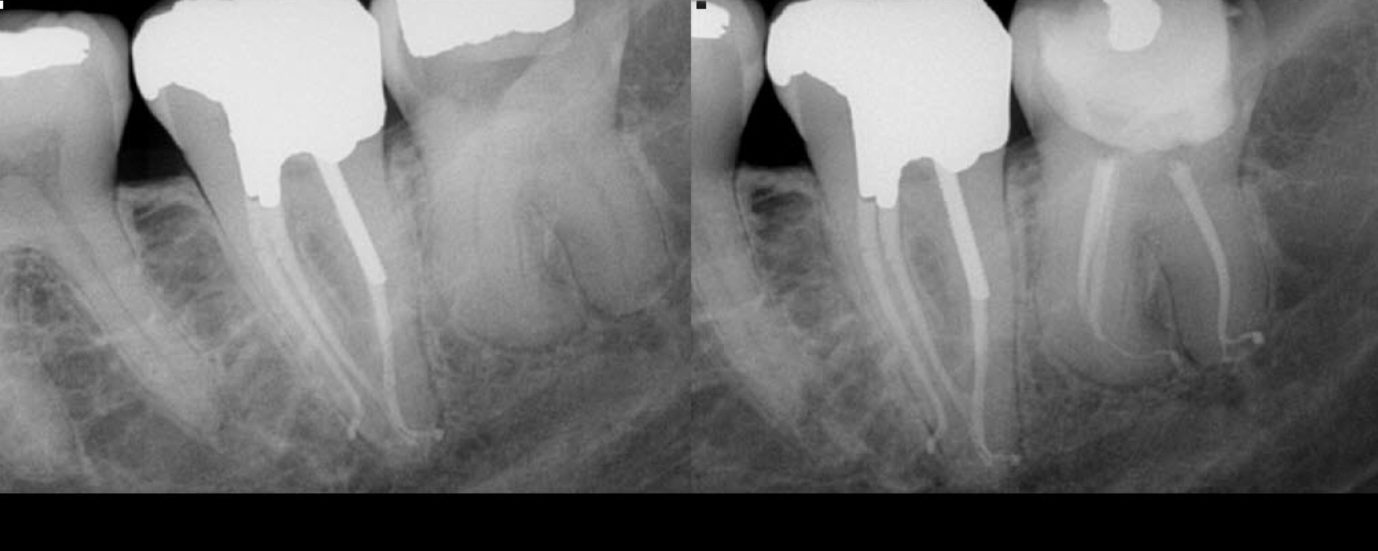

Just the routine endo on a 37 with a C shaped anatomy. Rapid flow technique used for obturation